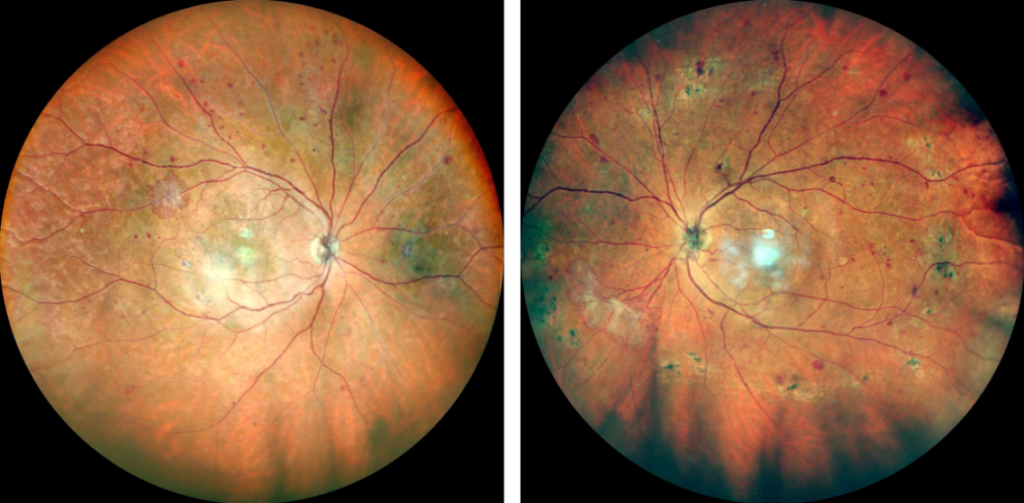

Sin embargo después de varios años de padecer la enfermedad (5 a 10 años, dependiendo de qué tan elevados son los niveles de glucosa y de la predisposición de cada paciente), empiezan a aparecer los primeros datos de retinopatía diabética no proliferativa (pequeños aneurismas y hemorragias en la retina), que no causan problemas en la visión, y son sólo evidentes a la revisión oftalmológica.

A medida que avanza el tiempo y no se controlen los niveles de glucosa, las lesiones en la retina aumentan en número e intensidad, como puede apreciarse en la fotografía. Aún en esta etapa donde hay muchas lesiones, la visión del paciente puede estar intacta.

En la etapa no proliferativa (es decir, en etapas iniciales) no se requiere tratamiento, dado que el riesgo de perder la visión es bajo.

Si se diagnostica retinopatía diabética proliferativa (es decir, la fase más avanzada), debe realizarse fotocoagulación de la retina con rayo láser. Este tratamiento tiene como finalidad disminuir las necesidades de oxígeno y nutrientes de la retina, y hacer desaparecer los neovasos, para evitar las complicaciones más serias de esta enfermedad.